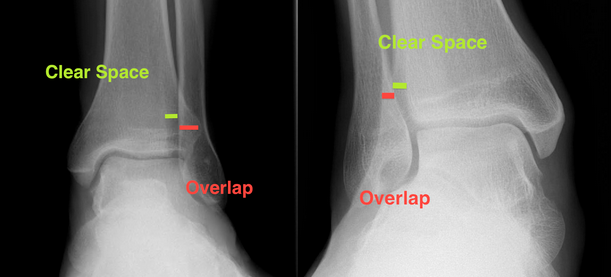

What are the normal values for ankle x-rays with respect to:

Medial clearspace

tib-fib overlap

tib-fib clearspace

Medial clearspace: = 4mm

Tib-fib clearspace <6mm on AP & mortise

Tib-fib overlap >6mm on AP & 1mm on mortise